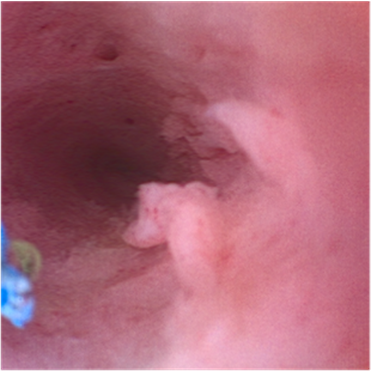

Methode: Die flexible Urethrozystoskopie bei Erstvorstellung zeigte multiple kondylomähnliche Veränderungen von der bulbären bis distalen Harnröhre ohne V.a. tiefe Infiltration oder Kontaktvulnerabilität. Bei einer erneuten flexiblen Urethroskopie in Intubationsnarkose wurden die Läsionen mittels Laser abgetragen. Zwei Wochen danach begann die ambulante Applikation einer 5%-igen 5-FU-Lösung in die Harnröhre. Der Patient erhielt acht Gaben mit einer Einwirkzeit von 30 Minuten im wöchentlichen Abstand, eine Gabe wurde wegen einer Covid-Infektion verschoben.

Abbildung 1 [Abb. 1]